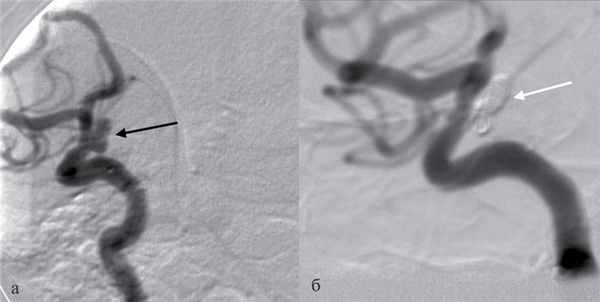

Рис. 1. Ангиограммы (DSA) пациентки с аневризмой параклиноидного сегмента правой внутренней сонной артерии. а — исходная ангиограмма в косой проекции (аневризма указана черной стрелкой); б — ангиограммы после тотальной окклюзии аневризмы микроспиралями (белая стрелка). На ангиограммах отсутствуют признаки вазоспазма.